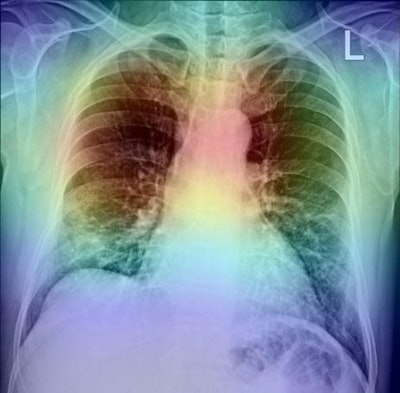

In addition, to further analyze the proposed method, the researchers used gradient-based class activation mapping (GradCAM) to represent the AI model's decision area on a heat map, which they suggested could help radiologists evaluate the chest area more accurately.